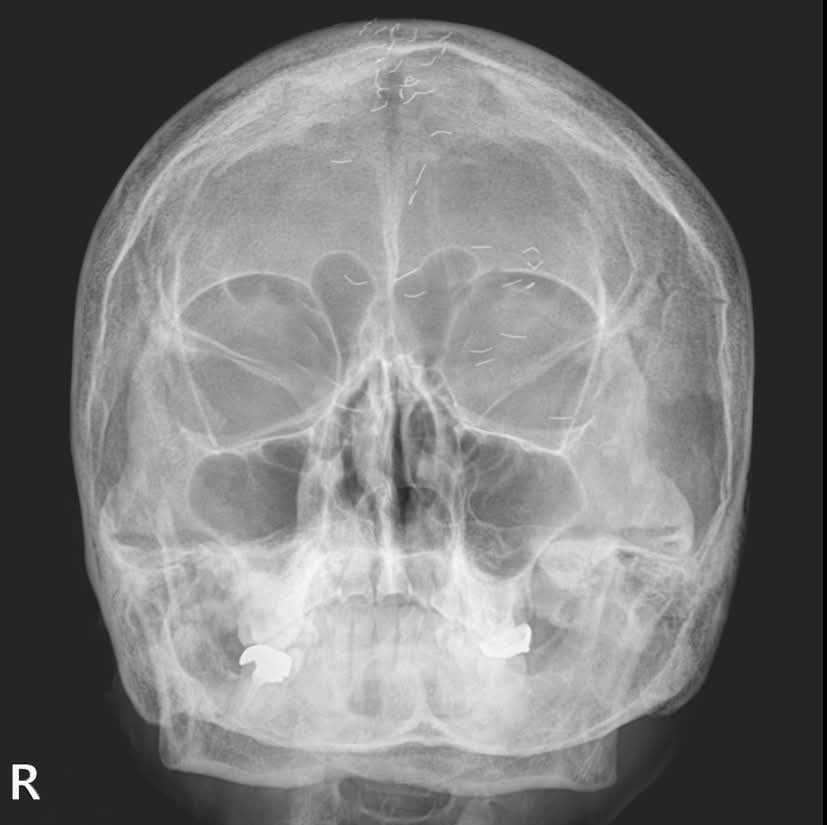

(의정부=뉴스1) 양희문 기자 = 60대 한국 여성 머릿속에 기생충처럼 보이는 수많은 이물질이 흩어져 있는 엑스레이 사진이 공개됐다. 이는 얇은 순금을 통증 부위에 주입하는 '금침요법'으로 인해 생긴 것으로, 이물질이 남아 있는 상태에서 시행할 경우 염증 악화와 2차 감염으로 이어질 수 있다.

양 과장은 "60대 여성 환자의 엑스레이에 1㎝ 크기의 수많은 이물질이 보였다"며 "기생충인가? 전기칩인가? 외국이었다면 특이한 환자 사례로 올랐을 것"이라고 적었다. 이어 "하지만 한국 의사라면 보자마자 헛웃음을 짓는다"며 "이물질의 정체는 기생충이나 전기선이 아니라 금침 자국이었다"고 했다.

금침요법은 금실매선요법을 말한다. 얇은 순금을 1cm 미만의 길이로 등분한 뒤 통증 부위에 주입하는 치료법이다. 한 번 주입한 금실이 해당 부위를 지속해서 자극해 치료 효과를 높인다고 한다. 그러나 몸속에 잔여 이물질이 남아 있으면 염증 악화와 2차 감염 등으로 이어질 수 있다.

양 과장은 해당 환자에게 '긴장성 두통' 진단을 내렸다. 그는 "뇌 MRI(자기공명영상)와 MRA(자기공명혈관영상) 검사는 정상이었고, 출혈·뇌암·뇌경색은 확실히 아니었으니 긴장성 두통이 확실했다"며 "환자에게 너무 걱정하지 말라고 했다"고 전했다.